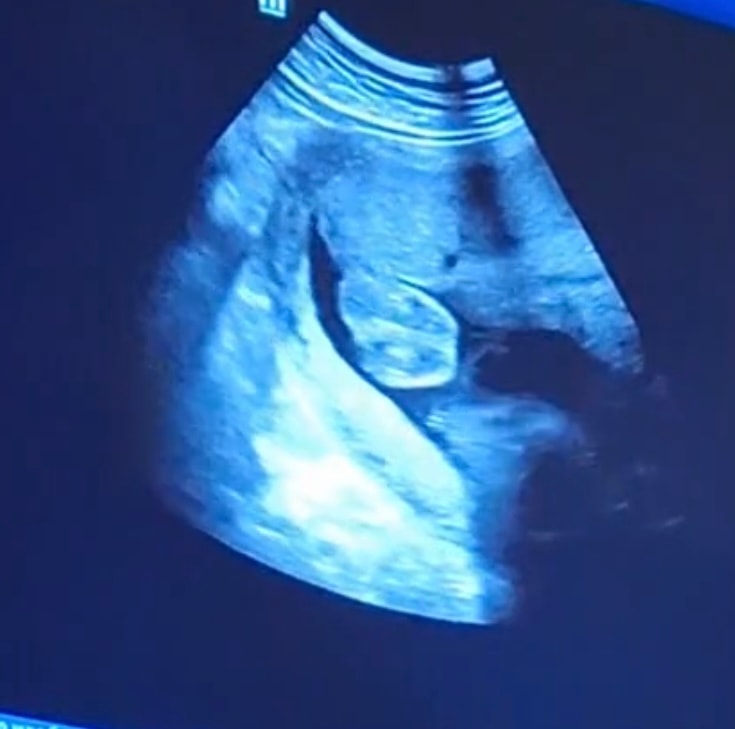

Пол малышаВсе здравствуйте, хотелось бы узнать у вас ваше мнение потому что сама уже в замешательстве. Я на 35 неделе сходила на 3 -е узи и мне сказали что там 50\50 потому что писюна не видно , а четко видно толи мощенка толи половые губы .

Анна, анамалий нету до этого ребенок закрывался ножками и не давал смотреть . Сказали точно скажут на третьем узи .

Лика Абрамян, странно, как можно перепутать яички с половыми губами, там разница кардинальная в размерах. Сделайте узи в другом месте